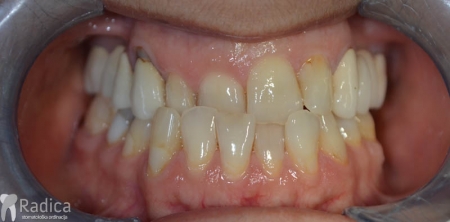

U galeriji slika su prikazani klinički slučajevi ovakvih odraslih pacijenta bilo da se radi samo o ortodontskoj terapiji ili predprotetskoj ortodonciji.